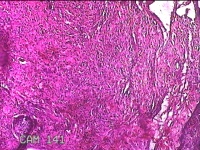

双侧眼睑结节

性别

男

年龄

52岁

临床诊断

眼睑皮赘

一般病史

发现双侧眼睑结节5年余,无疼痛及不适。

标本名称

大体所见

灰白暗红色结节0.8x0.7x0.3cm两个,表面糜烂,切面灰白粉红色,质软。

不具诊断价值。